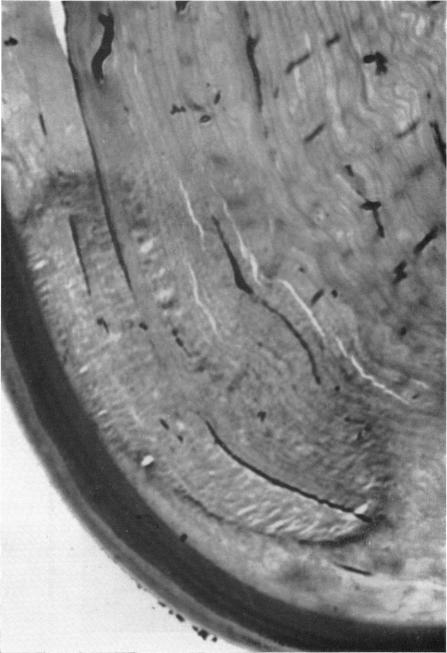

Hereditary deep dystrophy of the cornea (polymorphous).

Trans Am Ophthalmol Soc. 1969;67:235-64.